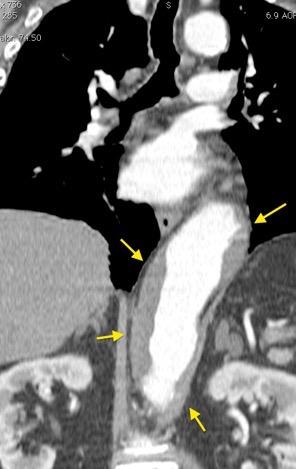

“Draped aorta”.

Indica rotura aórtica reciente. Se manifiesta por una pared aórtica posterior o el contacto con el borde lateral vertebral borrados por la hemorragia.

Rotura aneurisma de Aorta descendente.

Dolor. (10 días antes: "Rotura inminente”)